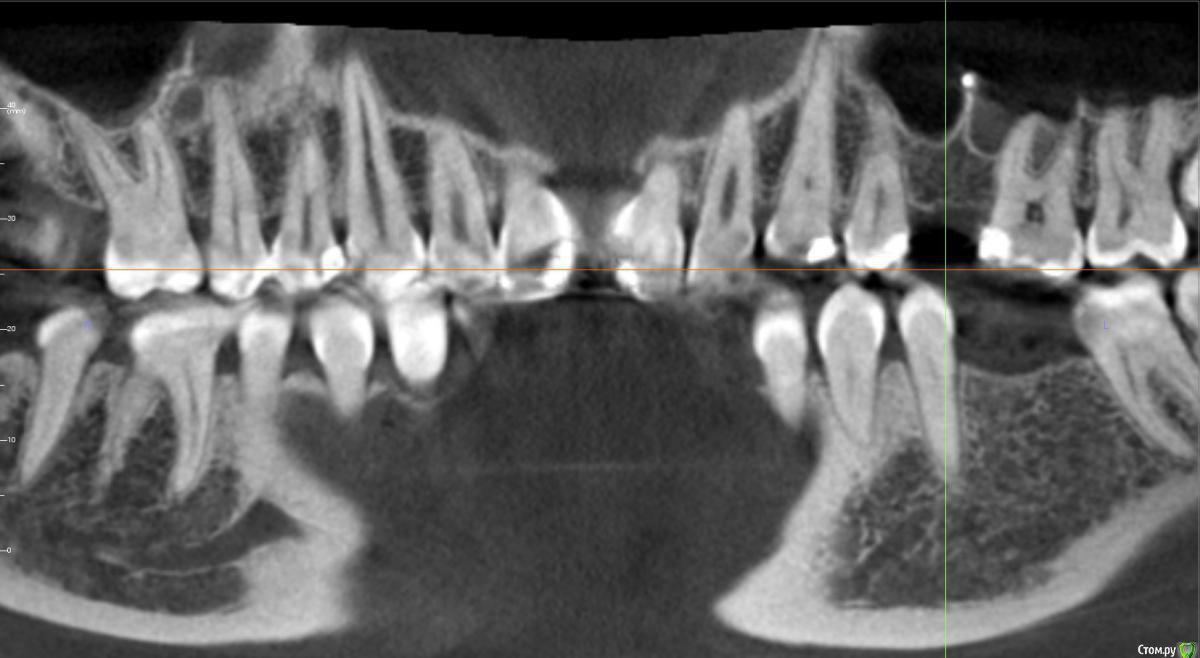

kamranchick Опубликовано 24 июля, 2017 Поделиться Опубликовано 24 июля, 2017 Ребятулечки, а можно тут как то поставить имплантат, без инвазии?В принципето молоток приветствуется если он тут сработает и сработает ли.хочу поставить 3.5 на 8.5 Ссылка на комментарий

kamranchick Опубликовано 24 июля, 2017 Автор Поделиться Опубликовано 24 июля, 2017 Сработает. Комп рисует без 1,5-2 мм, так что очень даже. Апикально кость с фрезы прям в перегонку стукнуть?))) Ссылка на комментарий